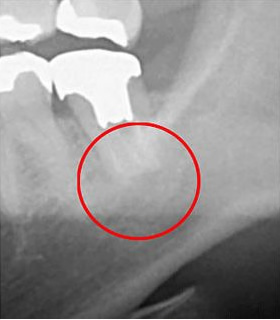

下の画像は、CTとレントゲンで同じ患部を撮影し、比較したものです。

左がCT、右がレントゲンです。

左の画像では赤い丸の中に、黒い影が見えます。しかし、右の画像にはありません。この影の正体は、神経の炎症です。もしもレントゲンだけで検査をしていたら、この炎症には気が付かないまま治療を終えてしまったかもしれません。

初期の小さな炎症も見逃さず、適切に治療を進めるには、CTでの画像診断が欠かせないのです。